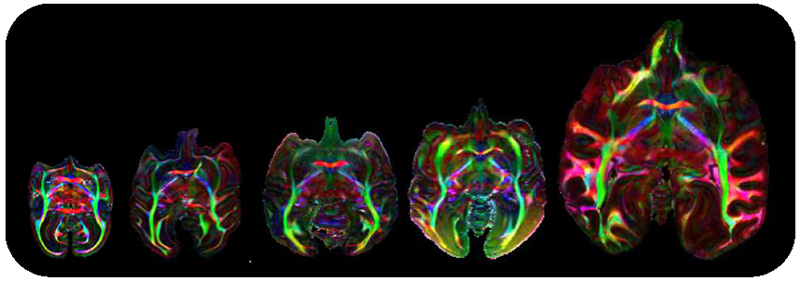

本プロジェクトおよび戦略的国際脳科学研究推進プログラムとの連携体制をもつ本研究グループは、世界最大級の霊長類脳標本コレクションを対象に、超高磁場MRI装置を用いて、脳標本を切り出すことなく神経線維の連絡性を可視化した拡散テンソル画像(diffusion tensor imaging; DTI画像)を撮像する顕微鏡的MRI技術を開発し、体重100gほどのマーモセットから体重38㎏のチンパンジーにまでわたる霊長類種の神経回路の多様性を全脳レベルで描出することに成功しました。本脳画像リポジトリは、今回の発表論文で第2フェーズへと入り、さらに、多様な霊長類の脳情報を包括的に提供することで、データ駆動型科学を通したヒト脳の特徴や精神・神経疾患の解明に貢献しています。

左から順に、ボリビアリスザル、ノドジロオマキザル、クロザル、チベットモンキー、チンパンジー